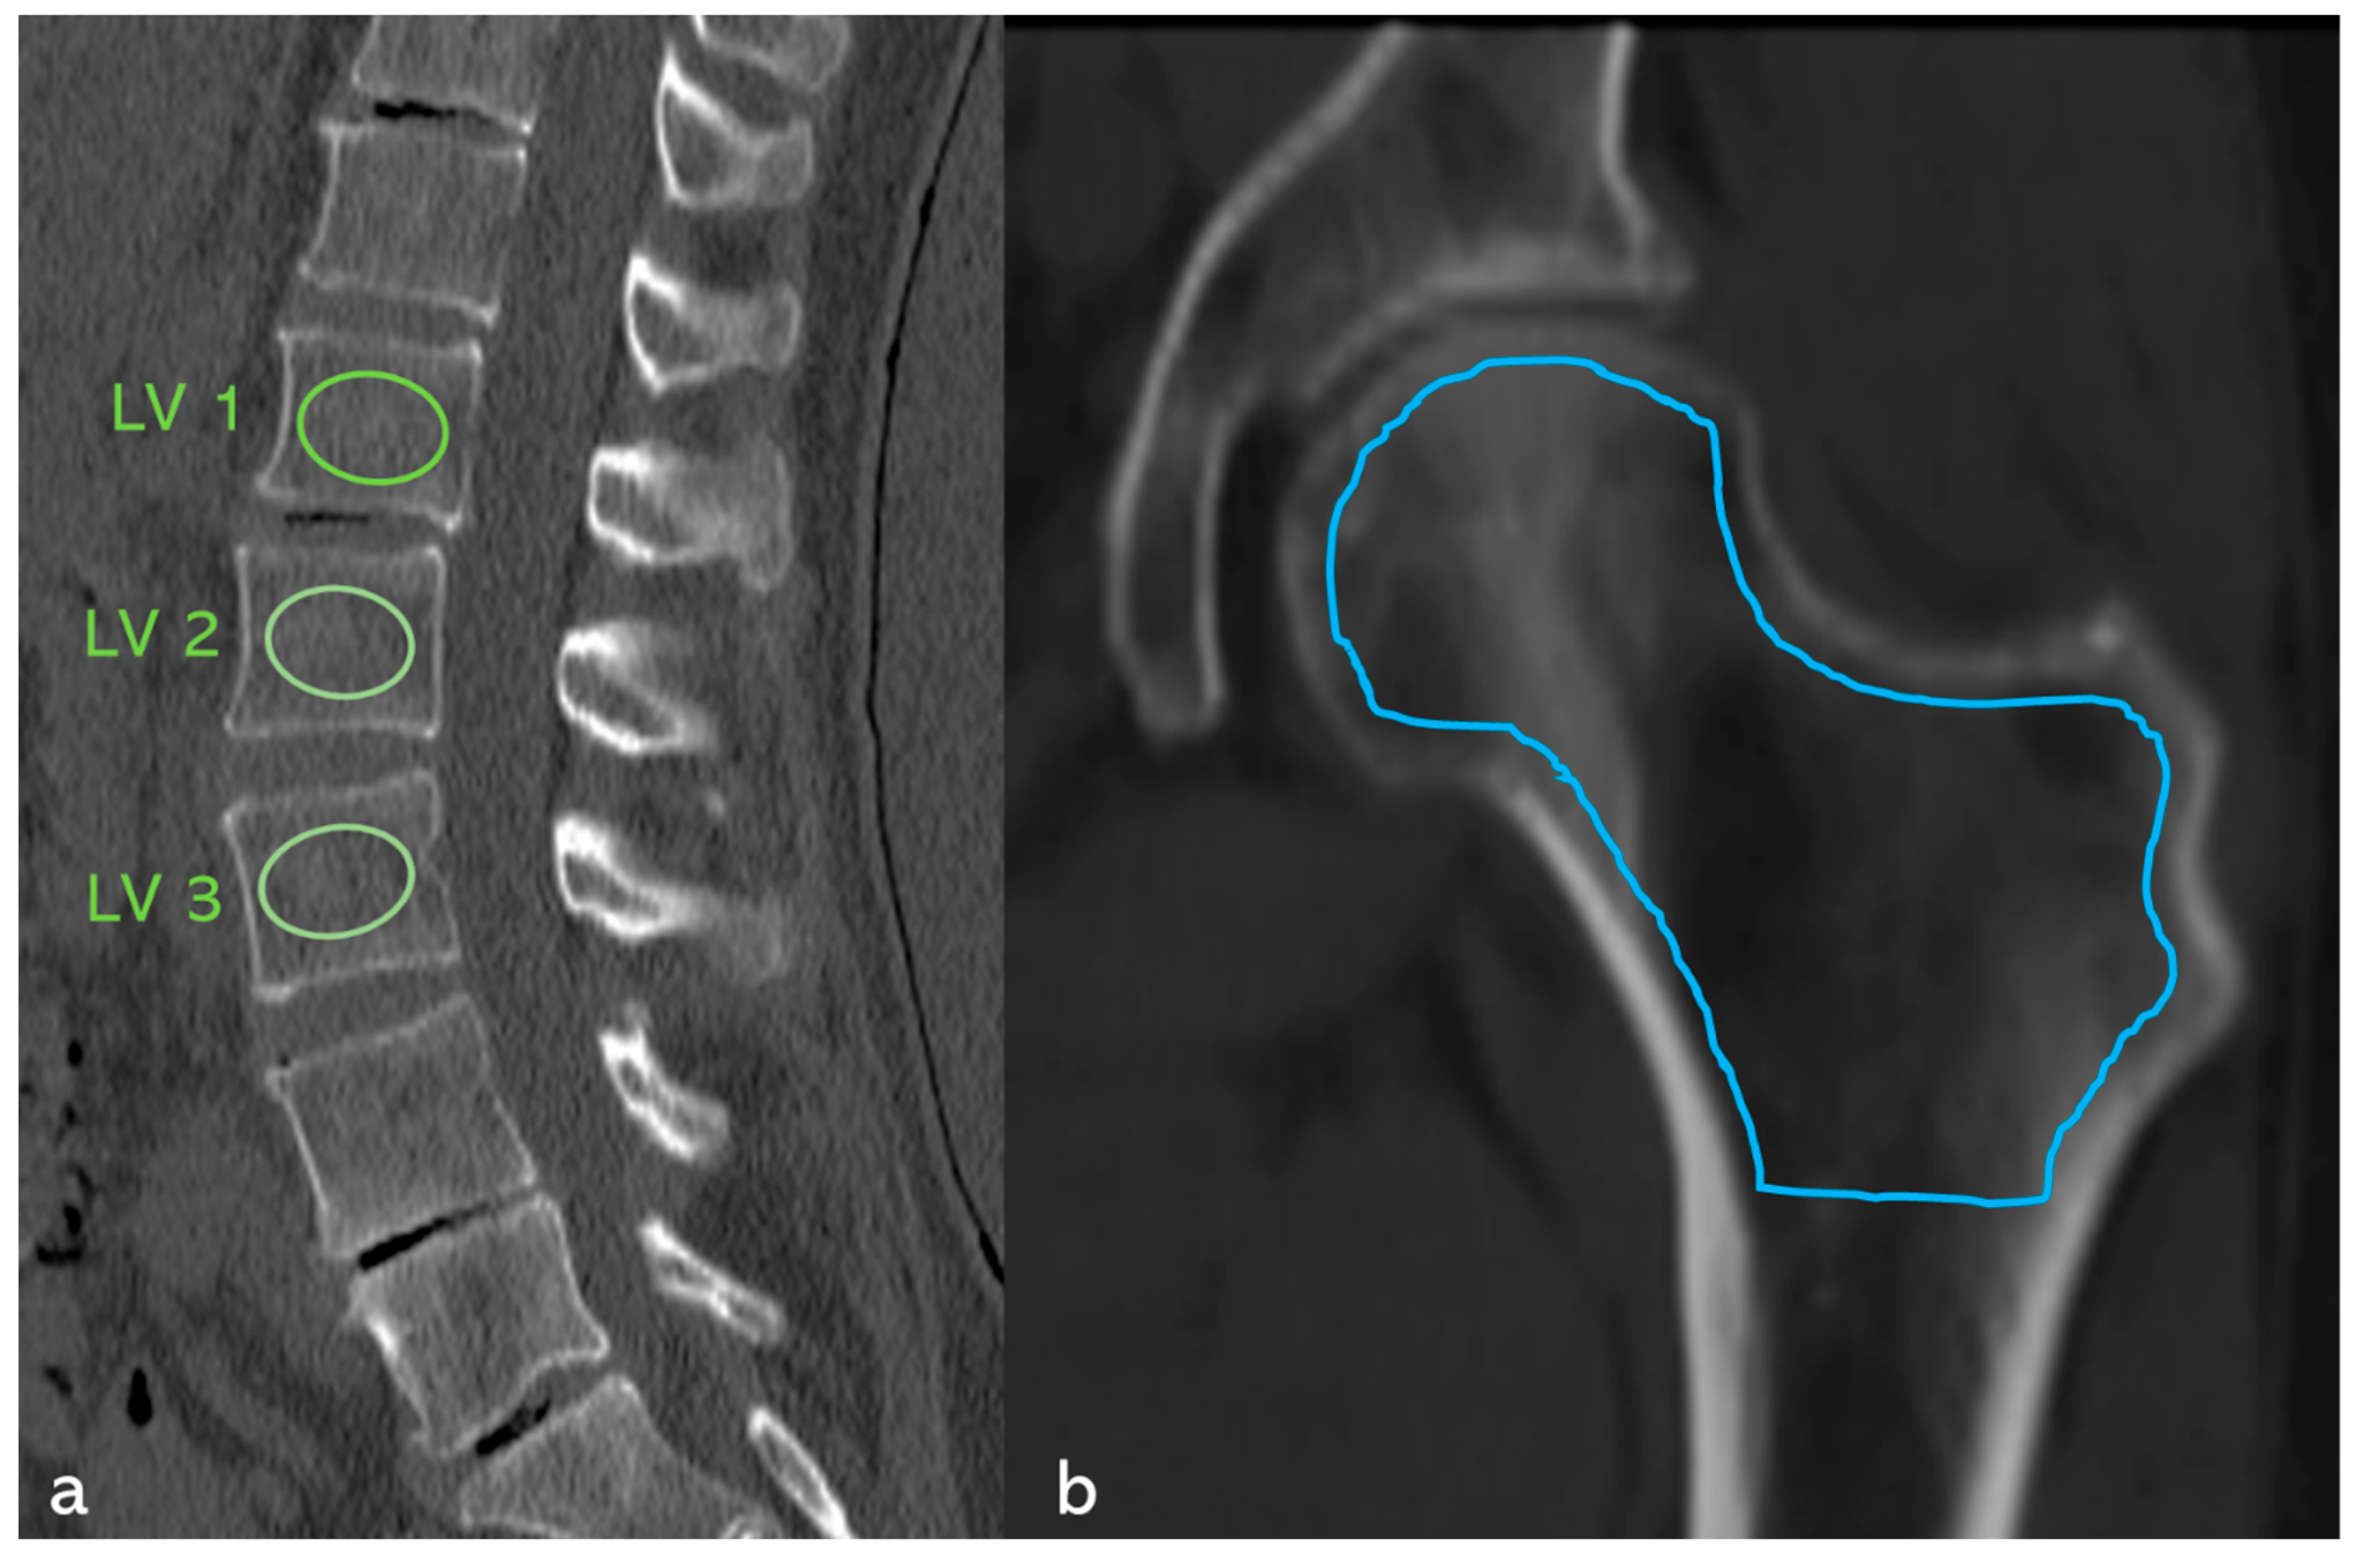

2.2. Determination of Bone Density

3.2.3. Fractures of the Axial Skeleton (Figure 6, Table 2)

| Affected vertebral bodies (Figure 6) (n) with at least one grade 1 vertebral body deformity according to Genant et al. [36] | 232 | 38 | 194 |